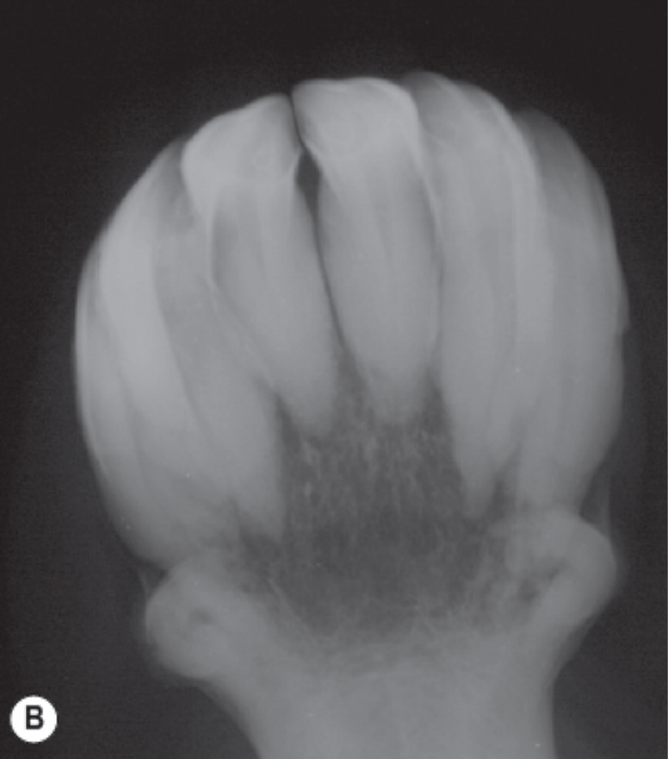

B: Radiographs of a 17-year-old pony with an abnormal amount of cells (cementum) around the roots.

Images by: Equine Dentistry, Third Edition. Section 3: Dental Disease and Pathology. Chapter 10: Equine Dental Pathology. J. Easly, P.M. Dixon and J. Schumacher, 2010.